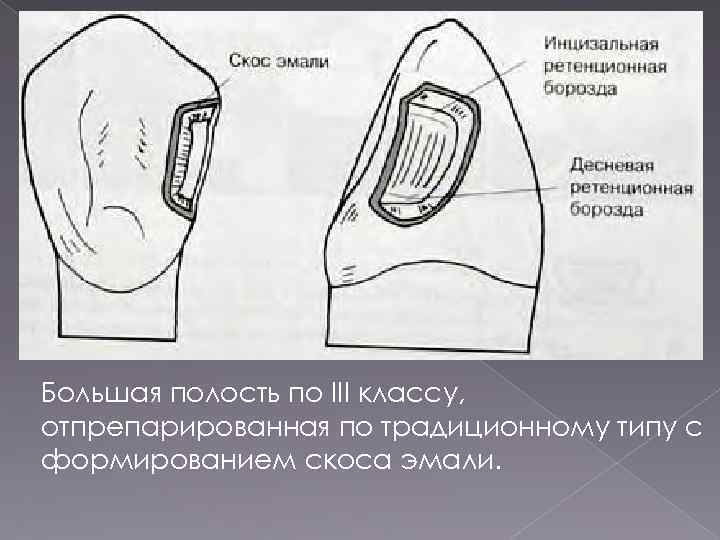

Препарирование кариозных полостей III класса: пошаговое руководство с фото